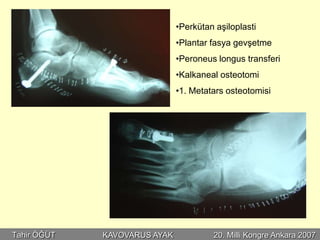

•Perkütan aşiloplasti

•Plantar fasya gevşetme

•Peroneus longus transferi

•Kalkaneal osteotomi

•1. Metatars osteotomisi